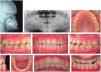

The patient had a brachifacial biotype, slightly increased facial lower third, the internal edge of the eyes coincided with the wings of the nose, mouth width matched the inter-iris distance, straight forehead, straight nasal septum, concave profile, augmented cervico-mental distance, decreased naso-labial and mento-labial angles, lip competence, thick lips, lips behind the aesthetic line, lower lip slightly everted and poor malar development (Figure 1).

At the intraoral analysis, he presented with an anterior crossbite, lower dental midline deviated with regard to the upper 2mm towards the right, overbite of -2mm overjet of -1mm, bilateral Class III molar relationship, bilateral canine class III, Ovoid upper and lower archform, mild crowding, rotations and a 3mm curve of Spee (Figure 2andTable I).

The panoramic radiograph evidenced the presence of the upper and lower third molars germs, apparently healthy alveolar ridges and good root length (Figure 2). The lateral headfilm was traced with Steiner cephalometric analysis resulting in a class III malocclusion cephalometric diagnosis due to a bimaxillary problem. The patient also presented a dental compensation through upper incisor proclination and lower incisor retroclination. The skeletal, dental and soft tissues characteristics provided the diagnosis of a skeletal class III patient due to a maxillary hypoplasia and mandibular prognathism (Table II).